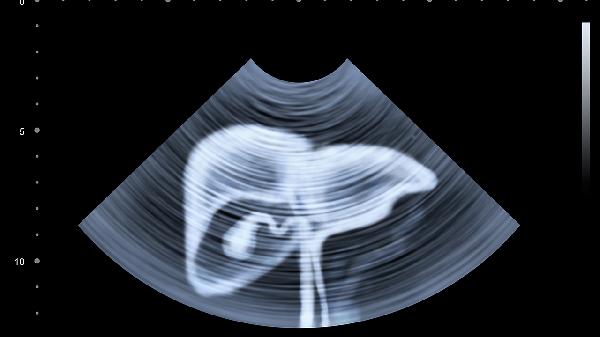

腹部鼓脹很大可能由消化不良、腸道積氣、腹水、腫瘤、肥胖等原因引起。

腹水多與肝臟疾病、心臟功能不全或惡性腫瘤有關(guān),表現(xiàn)為腹部明顯膨隆。治療需針對原發(fā)病,如肝硬化患者可使用利尿劑如呋塞米、螺內(nèi)酯,必要時進(jìn)行腹腔穿刺引流。飲食上應(yīng)限制鹽分?jǐn)z入,增加優(yōu)質(zhì)蛋白如魚、蛋的補(bǔ)充。定期監(jiān)測體重和腹圍變化。

腹部腫瘤如卵巢癌、肝癌等可能導(dǎo)致腹部鼓脹,伴隨體重下降、食欲減退等癥狀。需通過影像學(xué)檢查如CT、MRI明確診斷。治療方法包括手術(shù)切除、化療、放療等。飲食上應(yīng)高蛋白、高熱量,如牛奶、瘦肉等,避免辛辣刺激食物。心理支持對患者康復(fù)至關(guān)重要。